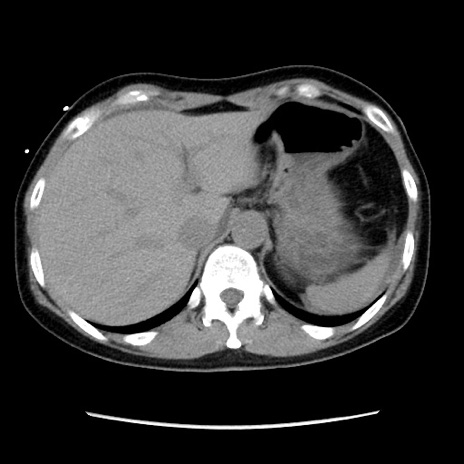

冠状断像